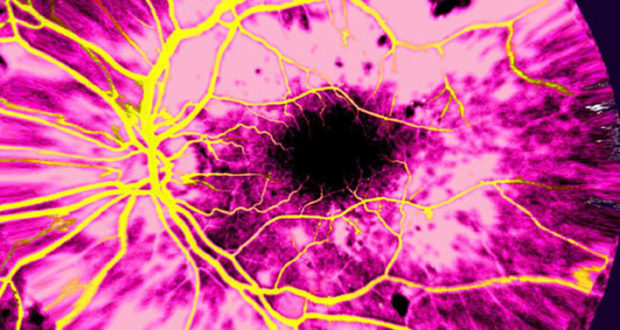

Priscilla Lynch reports on the long-awaited development of Ireland’s Diabetic Retinopathy Screening Programme.